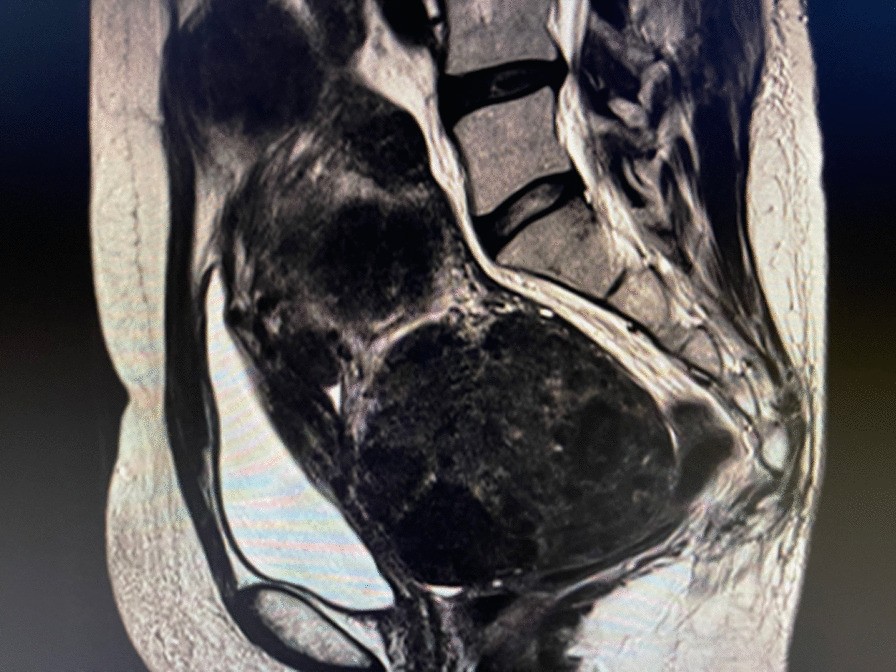

Fig. 2

Magnetic resonance images showing a significant reduction of the uterus after 6 months of oral relugolix (40 mg/day). After relugolix therapy for 6 months, diffused adenomyosis mostly disappeared compared to the baseline. It is noteworthy that the size of the uterus, including fibroid and adenomyosis, shrunken to 15 cm in length and 8 cm in thickness